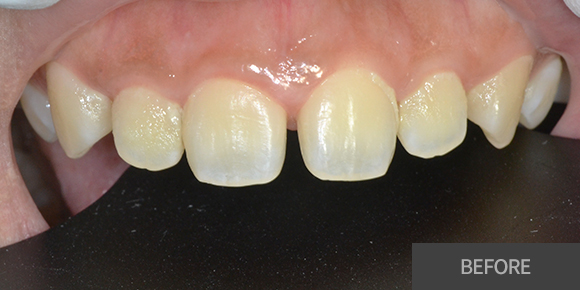

심미레진